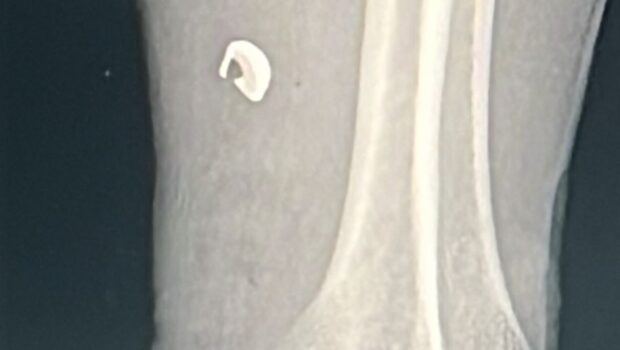

De acuerdo con la información recabada, el lesionado golpeó con un martillo dos cartuchos, provocando que uno de ellos detonara y le causara la herida. Tras los estudios médicos correspondientes, se confirmó que la lesión fue provocada por un proyectil de arma de fuego, quedando el fragmento incrustado en el antebrazo. El calibre del proyectil no fue determinado.